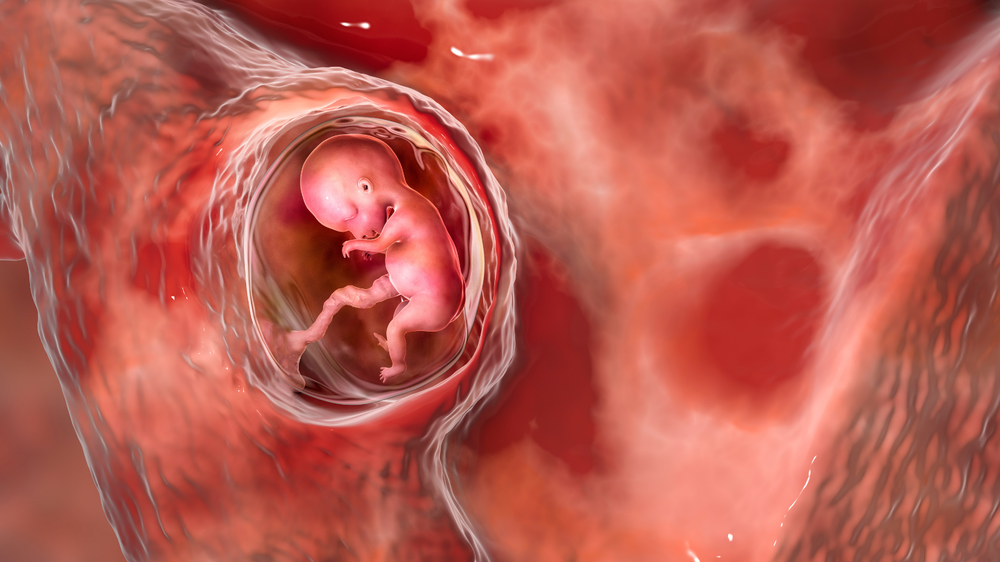

When you learn about the changes happening in your body during pregnancy, it can amaze you. Your body creates a life-sustaining bond with your baby right from the early stages to the very end of your pregnancy. It is responsible for supplying blood flow, nutrients and oxygen to nourish your baby. Understanding how blood flow gets established will ease your mind and also help you feel confident in this journey.

One of the most crucial changes in your body during pregnancy is the development of a connection between you and your baby. It helps your baby receive essential nutrients to support their growth, and also removes waste products.

What may surprise you is that your blood never actually mixes with your baby’s blood. Your body develops a new organ called the placenta to bridge the gap between the two of you.

The placenta connects with your baby’s body through an umbilical cord, which contains two arteries and one vein. They carry oxygen and nutrients to your baby and also remove the waste.

Your blood and your baby’s blood stay in separate systems, with the placenta acting like a filter and thus never mixing.

• Your blood flows into tiny spaces (called intervillous spaces) in the placenta.

• These spaces are surrounded by small blood vessels from your baby.

• Oxygen and nutrients pass through the thin walls from your blood into your baby’s blood vessels.

• At the same time, waste products from your baby pass back into your bloodstream to be removed.